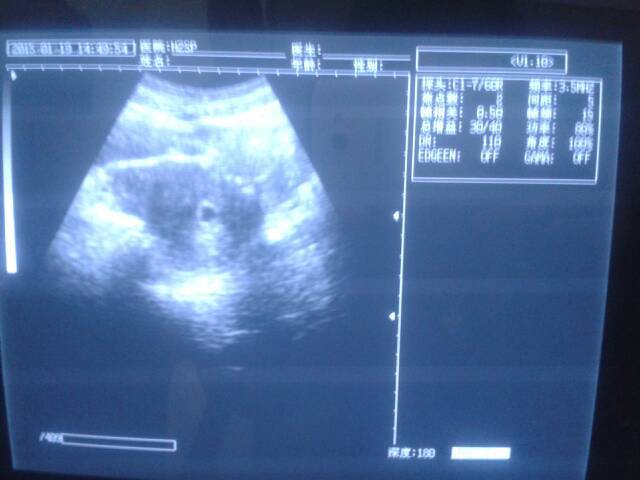

帮我看看是男孩还是女孩、我想要女孩 帮我看看是男孩还是女孩、我想要女孩 点击展开 \誰,螚了觧我の痛? 2015-01-19 20:24 为您推荐: 其他回答 这还能看出来么 好好的一辈子 2015-01-19 21:08 这怎么能看的出来 豆豆宝贝~ 2015-01-19 21:05 这个看不出来的,你可以去私人医院他们告诉你,你也可以去有熟人的医院 oοゞ季末 、念妳 2015-01-19 20:53 看不出来的。 荥洋嘛嘛 2015-01-19 20:43 怀孕五个月就能检查出是男孩还是女孩 现在宝宝太小还看不出来 小可爱x 2015-01-19 20:39 加载更多 相关问题 还是生男孩好呢,还是女孩好呢?我想要个男孩,老公想要个女孩 你说那个男孩女孩早知道准吗?我想要个女孩,现在怀孕四个月了,双顶项是37,股骨长是22 是女孩吗? 你好,我的月经是30号来的,我想要宝宝,不知道排卵期是哪几天,也不知道怎么样能要男孩女孩,你能帮我…